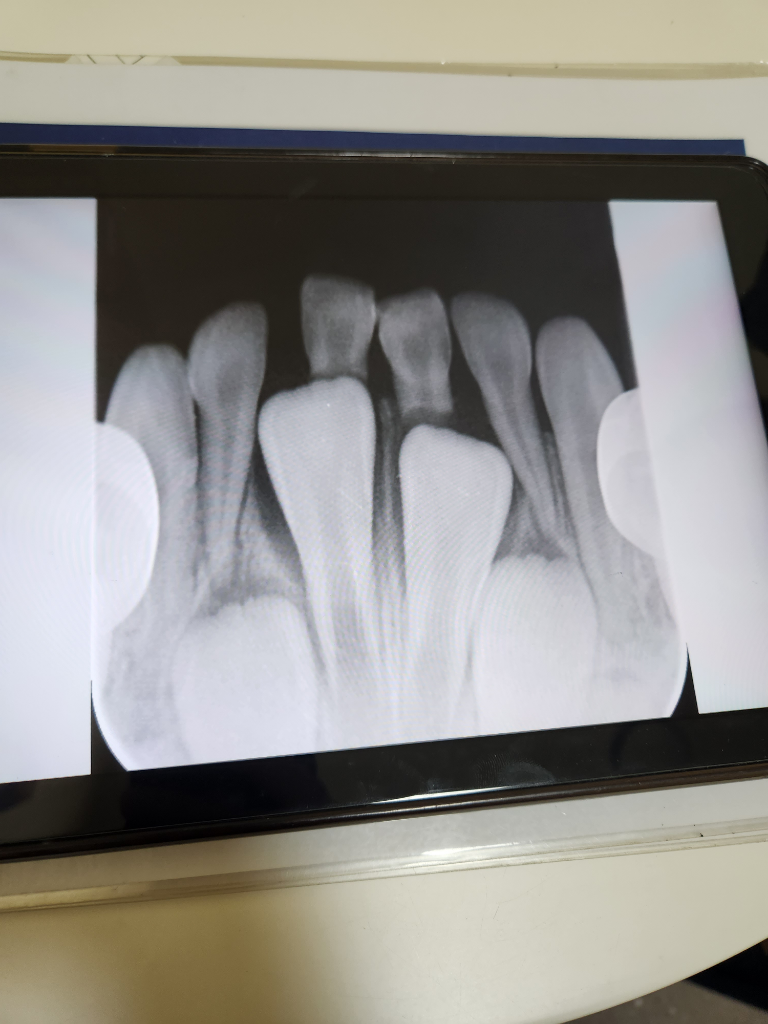

만5세 유치가 흔들리는데 4개를 뽑으라고하네요 뽑는게맞을까요?

일단 8월8일에 중간 두개 빼고왔거든요

내일이 예약(불소,검진, 옆에꺼뺄지말지는결정해야되요ㅜ)날이라서 갑자기 너무 고민되요ㅜㅜ사진보고 알려주세요

사진상으로 봤을 때 아래 앞니 영구치 올라올 공간이 부족한 것은 맞습니다

오른쪽 아래 첫번째 앞니는 영구치에 의해 뿌리가 많이 흡수되어서 많이 흔들릴 것 같고 왼쪽 앞니도 약간 흔들리는 상태였을것 같네요 빼는데 어려움은 크게 어려움은 없었을 것입니다

왼쪽 같은 경우 두번째 앞니 유치에 걸려있긴 합니다만 아직까지 두번째 앞니 유치들은 뿌리가 덜 흡수되었기 때문에 발치 중 환아가 조금 힘들어 할 수도 있습니다, 마취도 도포마취(바르는 마취)보다는 침윤마취(주사마취)를 해야 할 수도 있는데 무엇보다도 환아의 협조가 잘 되어야 합니다.

사진상으로 보면 가운데 두개 치아가 많이 흔들릴꺼 같은데 일단 2개 유치만 발치 하셔도 될것같습니다.

앞니 두개는 거의 다 맹출한것이라서 발치를 해도 문제가 되지는 않습니다.

아래 앞니 두개 이외는 아직 뿌리가 많이 남아 잇어서 일반적으로는 아래 치아가 어느정도 올라오고 뽑지만 부정교합이 생길수 있는 경우에는 미리 발치하는경우도 있어요.